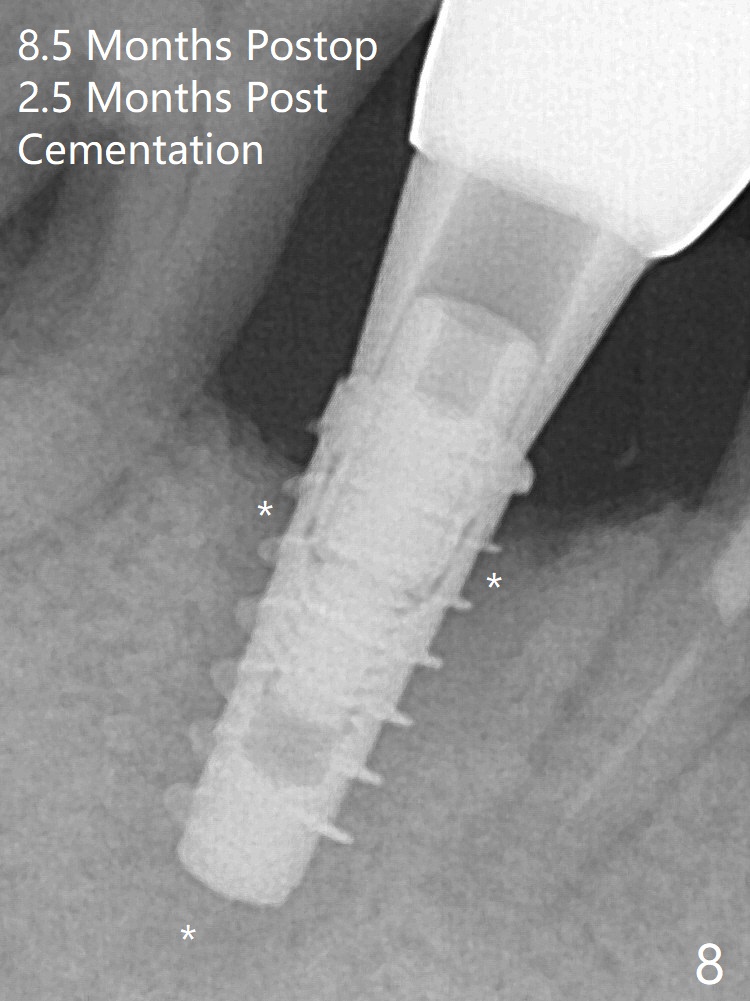

Final implant (Fig.5: 4x9 mm; red dashed line: socket) is placed 4 mm subgingival (supracrestal buccal; infracrestal lingual); Vanilla graft placed buccodistal (*). One month later, the abutment dislodges. The patient insists upon no provisional so that he can masticate on the right side, since there is no functional molars on the left side. A 4.5x3 mm healing abutment is placed. The implant appears to have osteointegrated 5 months postop (Fig7). A 4.5x5.7(4) mm pair abutment is placed for impression. The crown is loose 2.5 months post cementation (8.5 months postop); there is bone loss around the implant (Fig.8 *).